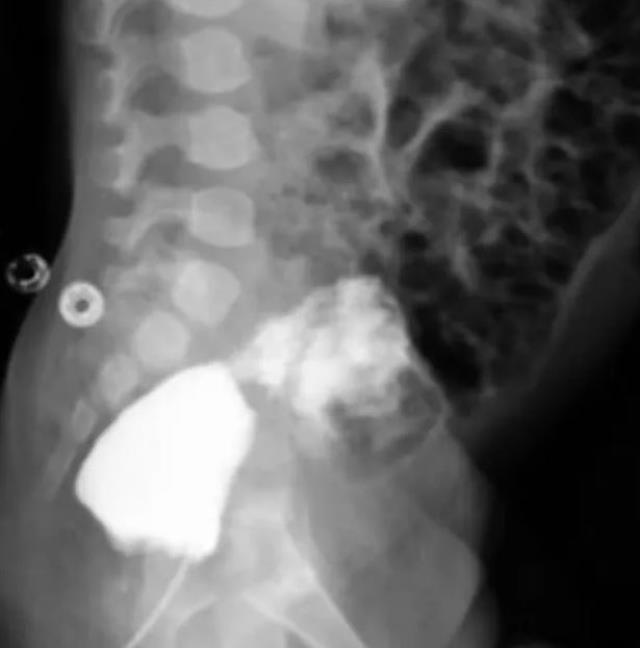

İran'da 30 milyonda bir görülen bir vaka meydana geldi. Hamile kadının karnındaki bebeğin cinsel bölgesine bakan doktorlar, bebekte ne kız ne de erkek cinsel organı bulunmaması nedeniyle büyük şaşkınlık yaşadı.

Kadının bebeğinin cinsiyetini öğrenmeye çalışan doktorlar, bebeğin cinsel organına baktıklarında büyük bir sürprizle karşılaştı. Çünkü bebekte ne erkek ne de kadın cinsel organı vardı.

Tıpta "Aphallia" adı verilen durumun 30 milyonda bir olasılıkta yaşandığı ve daha sonradan bebeğin gerçek cinsiyetine göre cerrahi işlem uygulandığı belirtildi.

İşte vakaya ait ultrason sonuçları: